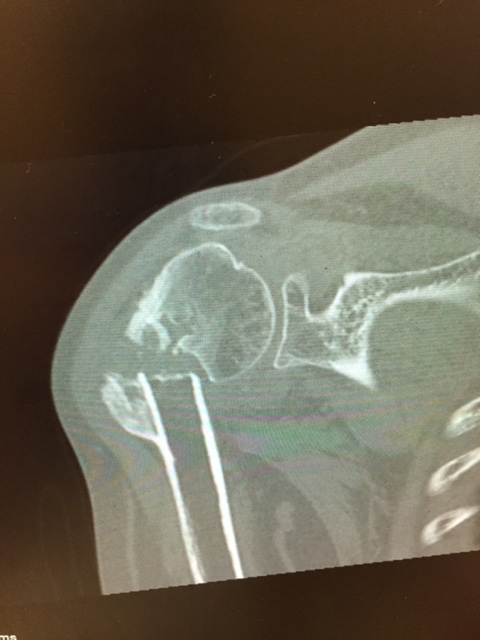

proximal humerus fracture Background ORIF with locking plate Arthroplasty Greater tuberosity fractures Lesser tuberosity fractures / avulsions Book traversal links for Proximal humerus fractures ‹ Pectoralis Major Tears Up Background ›